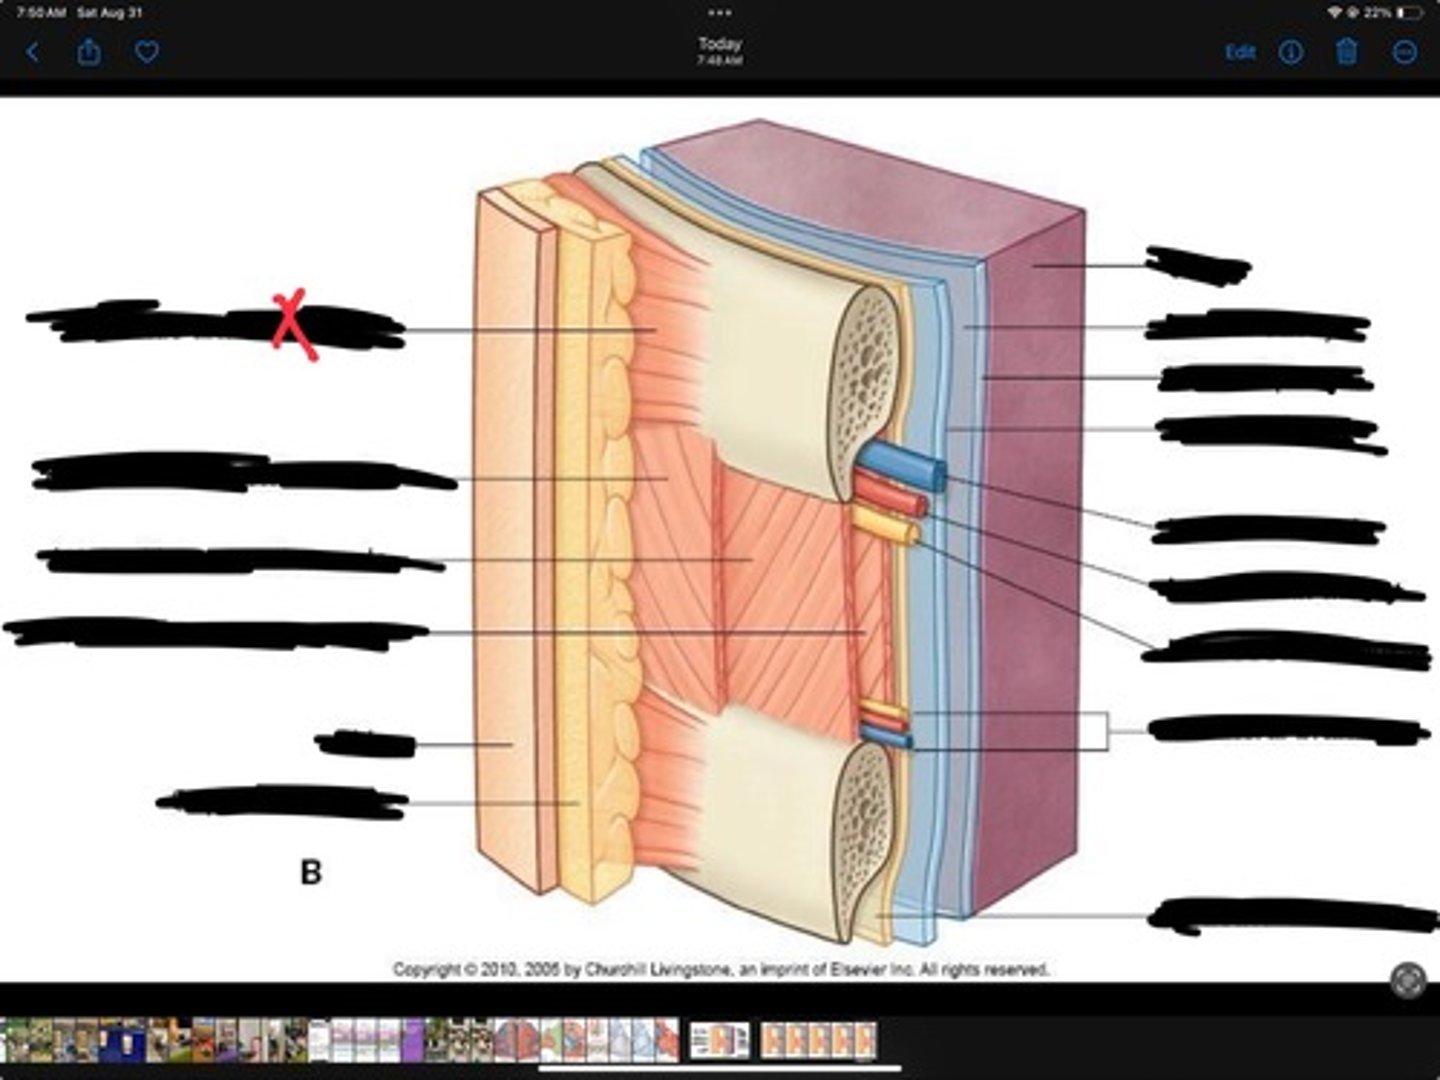

Innermost intercostal muscle

Skin

Internal intercostal muscle

External intercostal muscle

Serratus anterior muscle

Lung

Pleural cavity

Visceral pleura

Parietal cavity

Intercostal vein

Intercostal artery

Collateral branches

Intercostal nerve

Endothoracic fascia